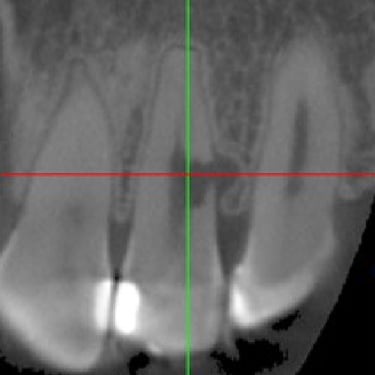

Calcificación Pulpar

La calcificación pulpar es la formación de depósitos de calcio dentro de la pulpa dental, que puede dificultar el tratamiento de conducto.

Los pacientes generalmente no tienen síntomas, pero pueden experimentar sensibilidad.

El tratamiento incluye la eliminación de los depósitos durante el tratamiento de conducto. Es importante tratarlo para evitar complicaciones durante el procedimiento.